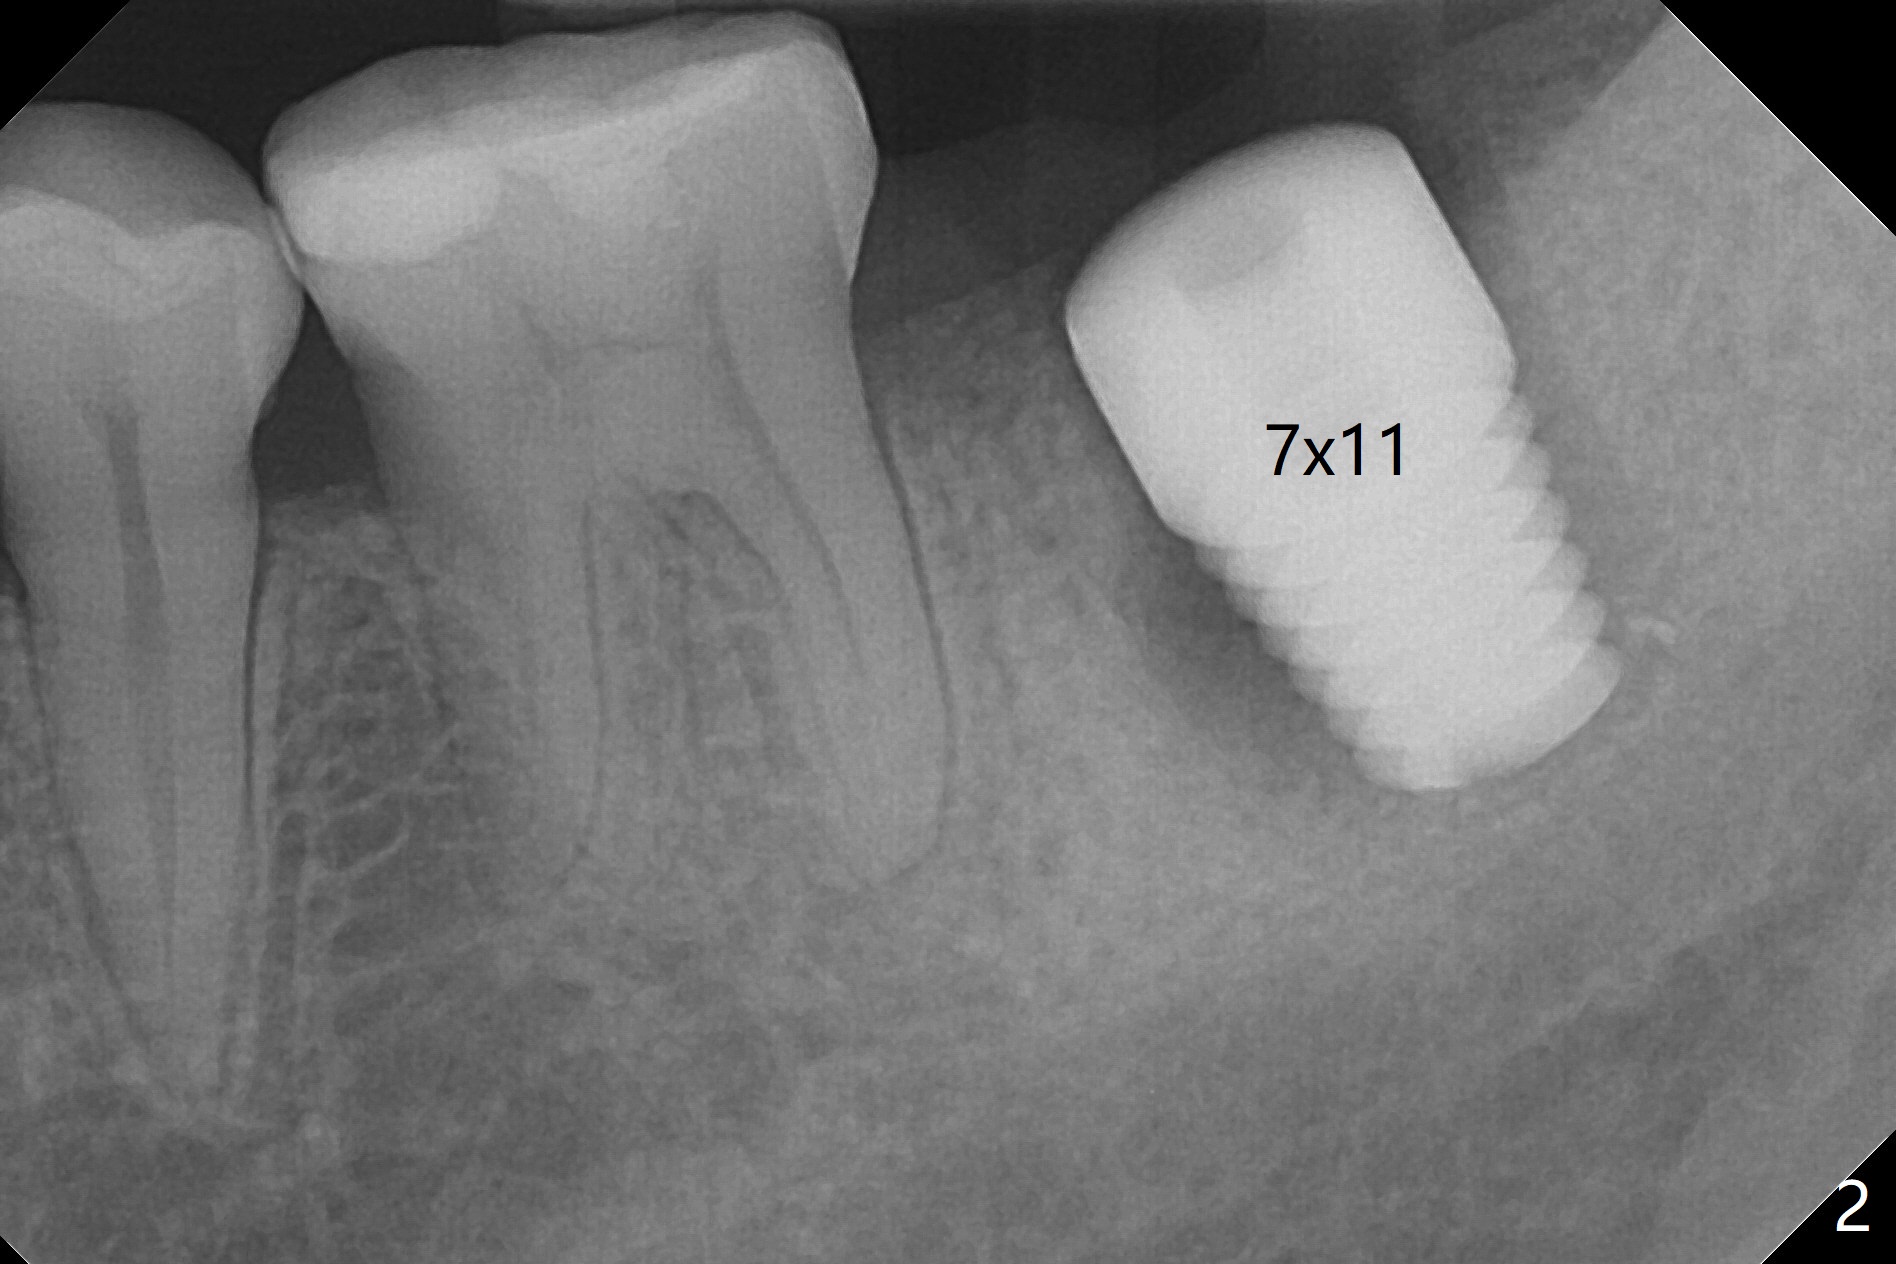

The patient with chronic buccal abscess at #31 is nervous.  After extraction, a 7x11 mm tapered implant drops into the single socket, which is close to the Inferior Alveolar Canal (Fig.2).  The bottom of the socket is sensitive to manipulation (explorer) after infiltration anesthesia.  A 8x14 mm tapered tap is placed without binding, neither is a 8x14 mm cylindrical implant.  The implant stability does not increase when Vera (.2-1.0 mm) or Vanilla (.5-1.0 mm) Graft is placed.  Socket preservation is finished with Collagen plug and 6-month membrane (Fig.3,4).